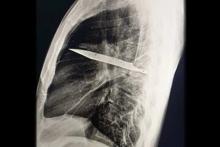

تصویربرداری با اشعه ایکس و سی‌تی‌اسکن نشان داد تیغه‌ای بزرگ از چاقو از پشت قفسه سینه وارد شده، بین دنده‌های پنجم و ششم گیر کرده و نوک آن تا جلوی قفسه سینه بین دنده‌های سوم و چهارم امتداد یافته است. شکستگی‌های ترمیم‌شده در استخوان کتف و چند دنده نیز مشاهده شد. هم‌چنین اطراف تیغه، بافت مرده و چرک تجمع یافته بود.